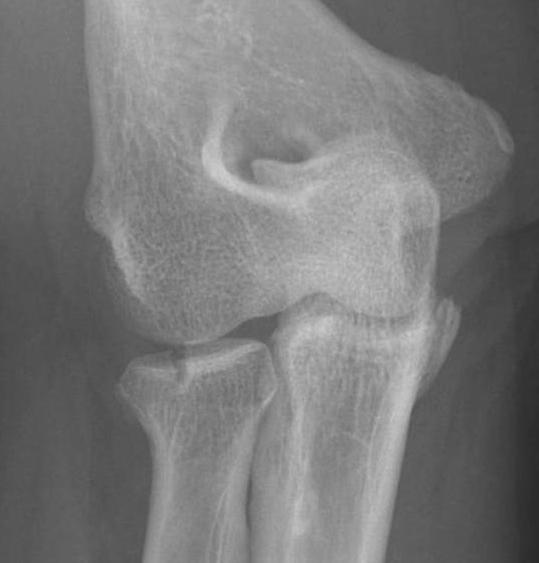

Overstuffing

| Lesser sigmoid notch | Symmetry of ulnohumeral joint |

|---|---|

|

Radial head shoulder articulate with lesser notch

Ensure no gapping of lateral ulnohumeral joint |

- cadaveric study

- increased medial ulno-humeral joint line gapping with overlengthening of 6 or 8 mm

- increased lateral ulno-humeral joint line gapping with overlengthening of 2 mm